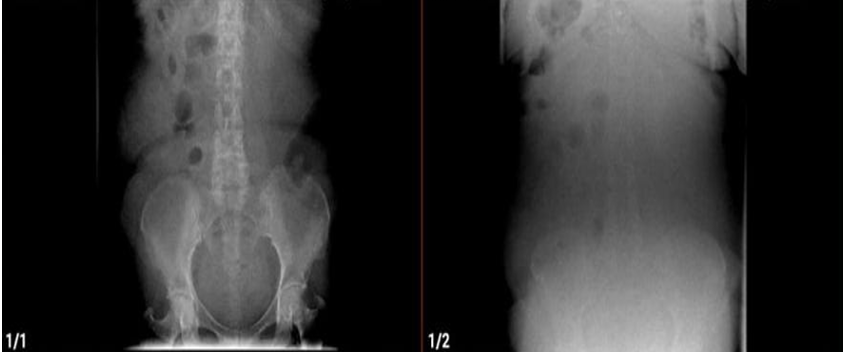

En los estudios de imagen la radiografía de abdomen: no se evidencian signos de obstrucción intestinal, se aprecia algo desplazadas las asas intestinales hacia el hemi-abdomen derecho (figura 1).

Figura 1. Radiografía de abdomen